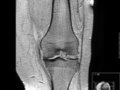

Остеоартроз: боль и разрушение?.. Остеоартрозом (ОА), который представляет собой самую распространенную форму поражения суставов человека, страдают от 10 до 13 процентов населения земного шара и приблизительно 15 миллионов человек в России. Это хроническое заболевание начинается медленно и незаметно с кратковременных болей в суставах, на которые человек не обращает внимания.